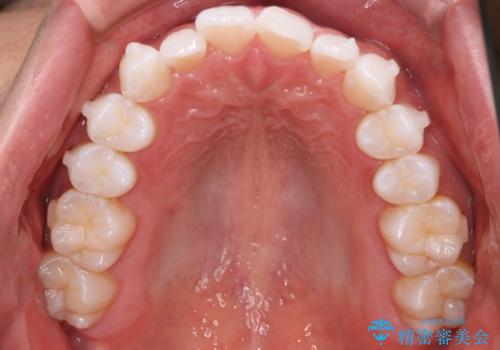

- 20代男性

- インビザライン

- がたつきが気になるとの事で来院されました。

目立たない装置で費用も抑えたいとの希望があったため、インビザラインにて治療をすることとなりました。

上下顎ともにIPR(歯と歯の間を削る処置)を行い歯並びを整える治療計画を立てました。

治療当初は、計画通りに治療が進むか心配でしたが、しっかりマウスピースを使用していただいたことで

治療期間も長引くことなく歯並びを綺麗に改善することが出来ました。

患者様の希望もあり、前歯の微調整で1回リファイメント(マウスピースの再発注)を行いました。